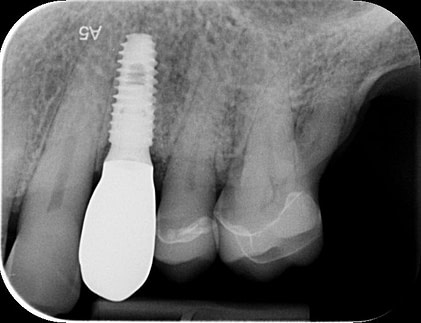

To better understand the patient's overall dental health, a full mouth CBCT scan was taken, confirming the presence of a bony defect in the area where tooth 24 had been surgically extracted.

Pre-surgical planning began with acquiring high-quality diagnostic data, including TRIOS intraoral scans and CBCT imaging. The data was imported into 3Shape Implant Studio, where I designed a virtual crown for tooth 24 and planned the precise positioning of the implant, considering critical factors such as sinus proximity, adjacent roots, bone density, and the location of the bony defect.

A radiographic assessment confirmed the proper integration and positioning of the implant.